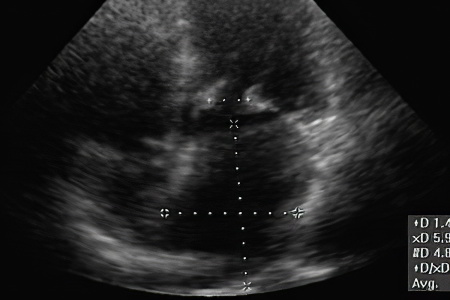

Оценивается работа легких и размеры печени. С помощью электрокардиограммы устанавливаются ритм сердца, тип аритмии, блокада и признаки ишемии. Фонокардиография используется для регистрации шумов и тонов сердца, а также для определения пороков клапанов. Для повышения точности диагноза применяются рентгенография сердца, эхокардиография, МСКТ или МРТ. Лабораторные исследования включают ревматоидные пробы, определение уровня сахара и холестерина. Обязательно проводятся клинические анализы крови и мочи.